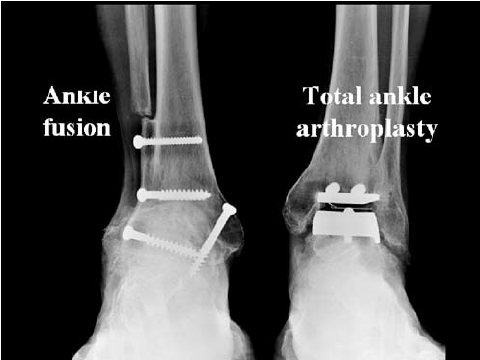

The 3rd idea is Arthroplasty surgery to the heel. Apparently some woman a few years ago already got one to increase her height.

62625252525bhshsgsg

Seaview Orthopaedic arthrodesis right and left ankle arthroplasty

This one seems like the most plausible.

Closest I've seen is this woman

Not enough people are publicizing it or pushing for it, but it's possible.